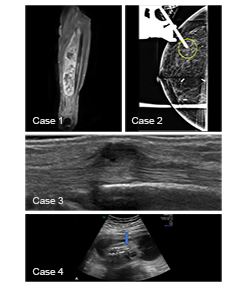

Stay up to date with the latest advancements in radiology. Read our exclusive newsletters, case studies and research papers authored by leading doctors.